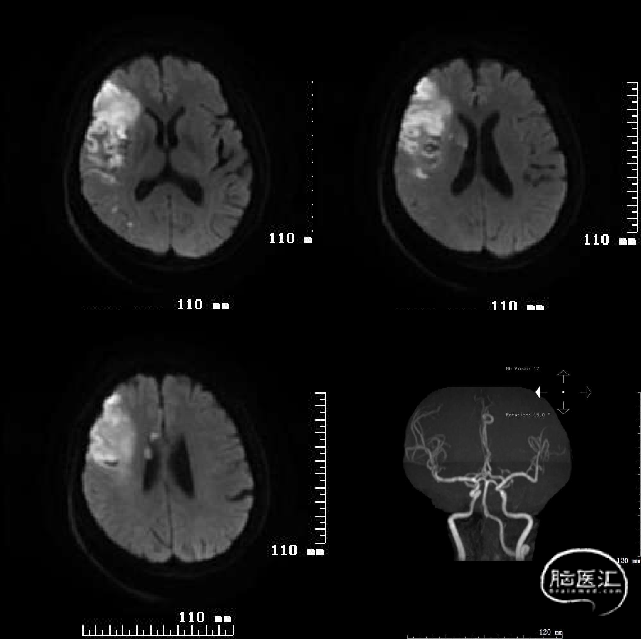

头颅MRI+DWI+MRA:右侧额颞叶及侧脑室旁急性脑梗塞,右侧大脑中动脉闭塞?右侧颈内动脉破裂孔段狭窄?

术后第二天复查头颅MRI